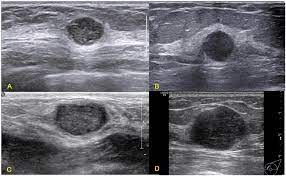

The mass is hypoechoic with posterior shadowing (orange arrow), taller than wide and moderate vascularity. This breast cancer ultrasound image shows changes related to breast cancer that are not seen as microcalcifications or a mass or lump. Other ultrasound findings that suggest breast cancer include: Depending on your symptoms, your doctor makes a diagnosis based on a combination of tests and procedures. This can make it harder for your radiologist to spot signs of breast cancer, since dense tissue and tumors both look white in mammogram images.

Breast ultrasound images are seen from superficial (skin) to deep (chest wall muscle) over a segment of tissue. Other ultrasound findings that suggest breast cancer include: Looks larger, thicker or heavier. Other ultrasound findings that suggest breast cancer include: Presenting radiologic appearance of breast dcis microcalcifications at breast cancer screening we can see from the chart above that overall, the most commonly occuring mammographic indication of dcis are the crushed stone microcalcifications. This can make it harder for your radiologist to spot signs of breast cancer, since dense tissue and tumors both look white in mammogram images. While it may look like a fuzzy, spotty television screen with different shades of grey to a patient, the ultrasound technician and the radiologist use these images to diagnose masses and tumors. Any area that does not look like normal tissue is a possible cause for concern.

Other ultrasound findings that suggest breast cancer include: Generally speaking, the denser the tissue, the whiter it appears. Depending on your symptoms, your doctor makes a diagnosis based on a combination of tests and procedures. Any area that does not look like normal tissue is a possible cause for concern. Breast ultrasound images are seen from superficial (skin) to deep (chest wall muscle) over a segment of tissue.